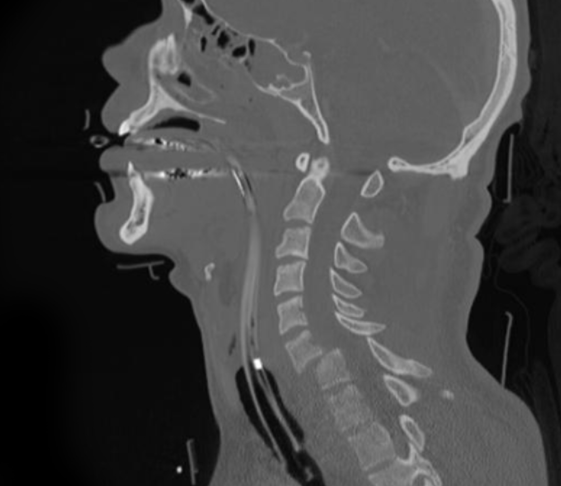

스마트폰를 손에서 놓지 않고, 하루종일 컴퓨터 모니터를 보며 생활하는 현대인들의 고질적인 질병 중 하나가 바로 목디스크입니다. 목디스크는 경추 추간판탈출증이라고도 부르는데, 경추는 7개의 등꼴뼈로 이루어진 척추의 맨 윗부분을 말하며 추간판은 디스크를 말합니다.

디스크는 우리 몸에서 목의 운동을 돕고, 목의 충격을 완화하여 척추뼈가 밀리거나 부딪히지 않도록 보호하는 쿠션과 같은 역할을 합니다.

하지만 나이가 들어가면서 목의 디스크 또한 노화되기 시작하고 핸드폰, 컴퓨터 모니터를 자주 사용함으로 인해 거북목, 일자목 등 체형의 변화가 오면서, 경추의 디스크가 후방으로 돌출되는 목디스크 질환이 생길 수 있습니다.

약물치료, 물리치료 및 주사치료가 효과가 없을 경우, 수술적 치료를 진행해야 합니다. 수술적 치료에는 대표적으로 내시경 신경감압술, 인공디스크삽입술 등이 있습니다.

내시경 신경감압술은 내시경과 수술도구를 1cm 미만의 절개부에 삽입하여 탈출한 디스크를 제거, 신경을 누르는 압력을 해소하는 수술입니다.

인공디스크 삽입술은 탈출한 디스크를 제거하고, 특수제작된 인공디스크를 삽입하는 방법의 수술로, 수술 이후 척추의 퇴행성 변화를 최소화활 수 있는 수술 방법입니다.